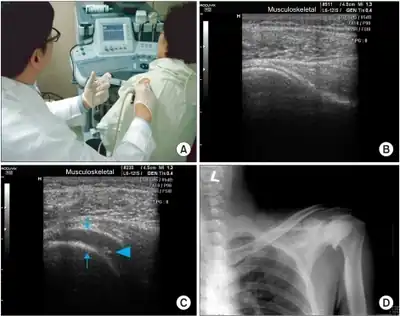

Sono-guided capsular distension. (A) Sono-guided capsular distension by the posterior lateral approach. (B) Before Sono-guided intra-articular injection at glenohumeral joint. (C) After sono-guided injection with capsular distension (arrow). The needle tip (arrowhead). (D) After steroid injection with capsular distension.

Adhesive capsulitis can be diagnosed by history and physical exam. It is often a diagnosis of exclusion as other causes of shoulder pain and stiffness must first be ruled out. On physical exam, adhesive capsulitis can be diagnosed if limits of the active range of motion are the same or similar to the limits to the passive range of motion. The movement that is most severely inhibited is external rotation of the shoulder.

Imaging studies are not required for diagnosis but may be used to rule out other causes of pain. Radiographs are often normal but imaging features of adhesive capsulitis can be seen on ultrasound or non-contrast MRI. Ultrasound and MRI can help in diagnosis by assessing the coracohumeral ligament, with a width of greater than 3 mm being 60% sensitive and 95% specific for the diagnosis. Shoulders with adhesive capsulitis also characteristically fibrose and thicken at the axillary pouch and rotator interval, best seen as dark signal on T1 sequences with edema and inflammation on T2 sequences.[10] A finding on ultrasound associated with adhesive capsulitis is hypoechoic material surrounding the long head of the biceps tendon at the rotator interval, reflecting fibrosis. In the painful stage, such hypoechoic material may demonstrate increased vascularity with Doppler ultrasound.[11]